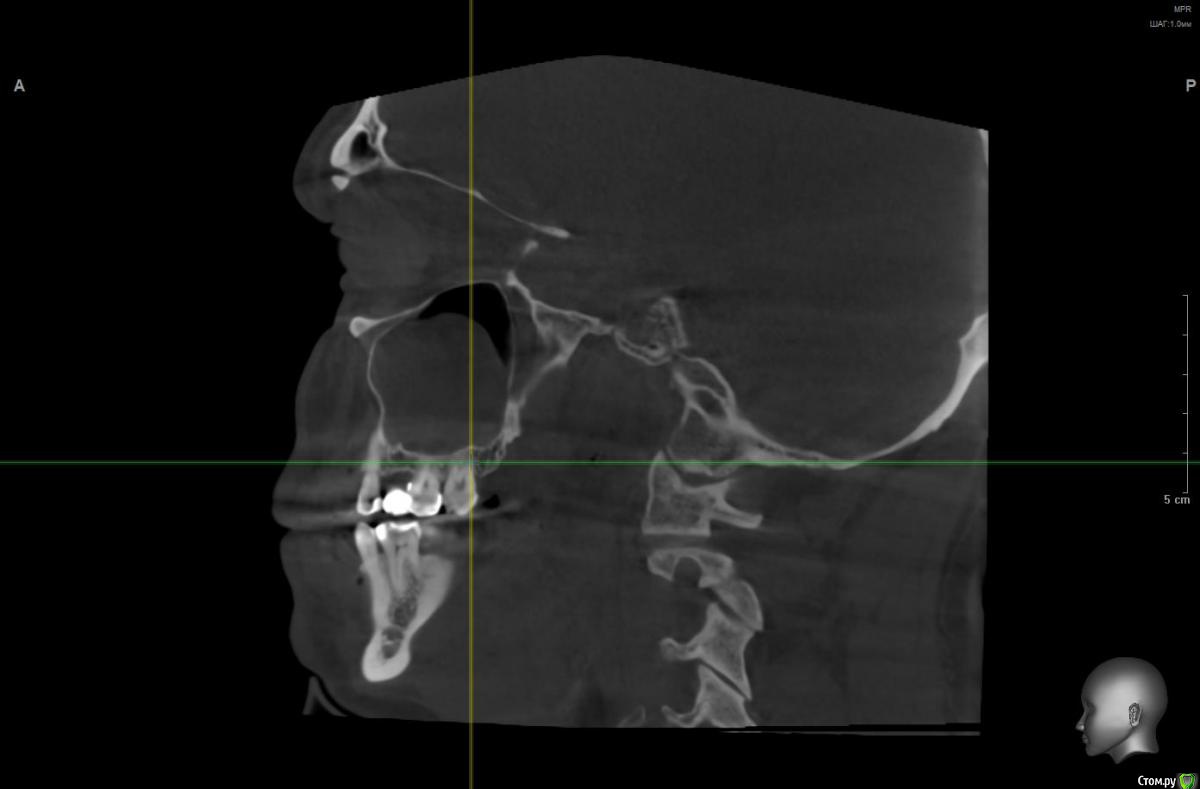

Sloleg Опубликовано 4 марта, 2019 Поделиться Опубликовано 4 марта, 2019 (изменено) Уважаемые доктора, здравствуйте! Если возможно, помогите, пожалуйста, советом. Был недавно на приеме у лора, сделал КТ на котором была обнаружена киста с признаками хронического одонтогенного синусита, и источника всех моих хронических воспалений и головных болей коими я периодически озадачивался. На приеме у стоматолога при изучении КТ, пришли к выводу, что проблема с верхнем зубом (6ка) леченным в 90х годах прошлого века резорцин формалиновым методом. Мое предложение вырвать эту 6 ку и поставить имплантат было отвергнуто т.к. для имплантата недостаточно костной ткани и без синус лифта не обойтись. Семерка была удалена несколько лет назад, 8ка кривая смотрит в сторону и в процессе участия не принимает. Таким образом при удалении 6ки вся нагрузка ложится на 5, 4 ку. в связи с чем имею большую печаль Хочу спросить хорошего эндодонта про шансы и возможности лечения. Очень хочу сохранить. P.S. Есть болле информативная КТ диагностика в полном формате всей челюсти. https://yadi.sk/d/hI3HWgsVHMTwUg Изменено 4 марта, 2019 пользователем Sloleg Ссылка на комментарий

wladdX Опубликовано 5 марта, 2019 Поделиться Опубликовано 5 марта, 2019 Корональная проекция Сагиттальная справа Сагиттальная слева 16 26 28 Ссылка на комментарий

kramer Опубликовано 5 марта, 2019 Поделиться Опубликовано 5 марта, 2019 В общем скачал я КТ. Что касается зуба 26, да, там есть признаки воспаления вокруг корней, лечить / удалять зависит от состояния тканей зуба и возможностей врача. Но лично мне не кажется, что этот зуб играет главную роль в возникшем гайморите. Обратите внимание, в области 8 зуба (см. срез) внутри пазухи есть некий очаг, содержащий неоднородные по плотности элементы (более светлые включения, а выше пузырьки воздуха). Снимок не особо четкий, но такое ощущение, что в области 8 зуба вообще нарушена целостность боковой стенки пазухи. Кроме того, с правой стороны все зубы в порядке, а явления гайморита тоже имеются (там вообще почти вся пазуха забита). Соустья с носом закрыты. В общем, в данной ситуации я бы более детально обследовал 8 зуб, если там все нормально, то пусть ЛОРы эндоскопически лезут в пазухи и убирают это все. Ссылка на комментарий